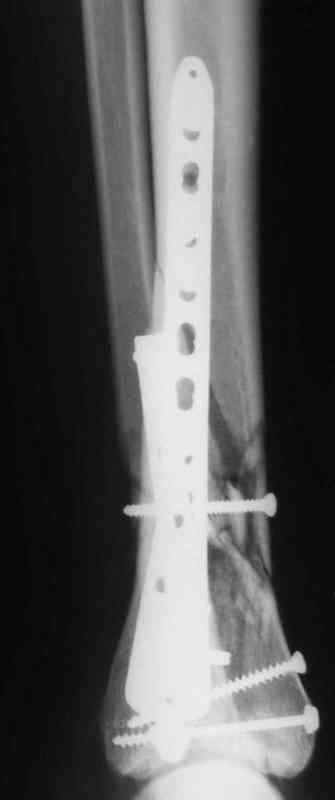

В настоящее время больной в реанимации по поводу Черепно Мозговой Травмы и состояние улучшается. Запланировал ушивание раны в пятницу, если позволит состояние мягких тканей и при отсутстви отека возможно удастся просунуть перкутанномедиальную пластину.

КТ пилона имеем.

Да кстати нашёл похожий случай для пилона.Малоинвазивная дистальная пластина LCP у вас я думаю есть опыт их использования ну очень хорошая. Очень стабильно получается.